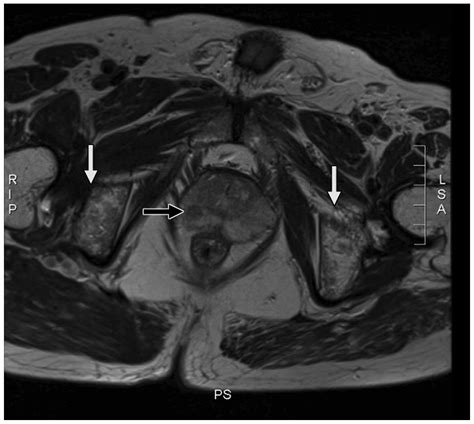

• T2-weighted imaging: Provides high-resolution anatomical images, allowing the radiologist to see the shape and size of the prostate clearly.

• Diffusion-weighted imaging (DWI): Measures the movement of water molecules within the tissue; cancerous cells, being more densely packed, restrict this movement, which shows up as a “bright spot” on the scan.

• Dynamic Contrast-Enhanced (DCE) imaging: Involves the injection of a contrast dye to observe how blood flows into the tissue, as tumors often exhibit distinct blood vessel patterns compared to normal tissue.